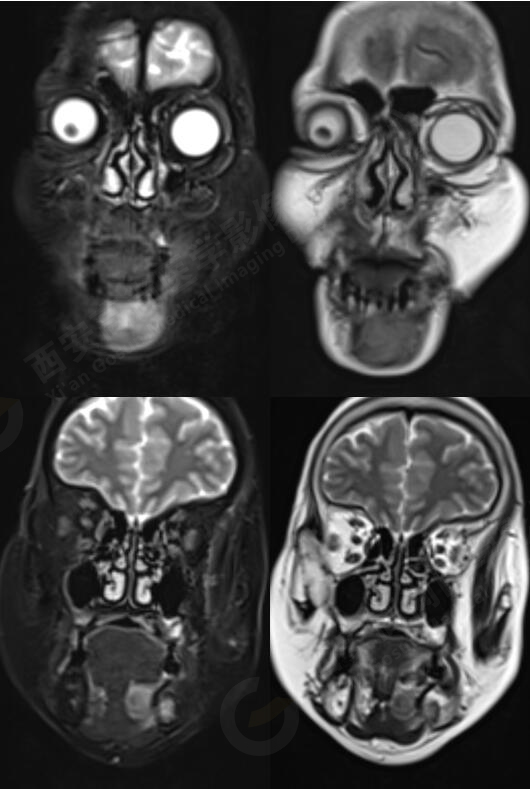

MR影像圖

MR平掃+增強(qiáng):左側(cè)口底部下頜骨周圍見大小約3.4cmX3.3cmX3.3cm的團(tuán)塊狀稍長(zhǎng)T1稍長(zhǎng)T2信號(hào),壓脂像上呈稍高信號(hào),病灶邊緣清晰,形態(tài)不規(guī)則,下頜骨骨質(zhì)破壞,強(qiáng)化掃描示:左側(cè)下頜骨周圍病灶呈不均勻明顯強(qiáng)化,邊緣強(qiáng)化為著。